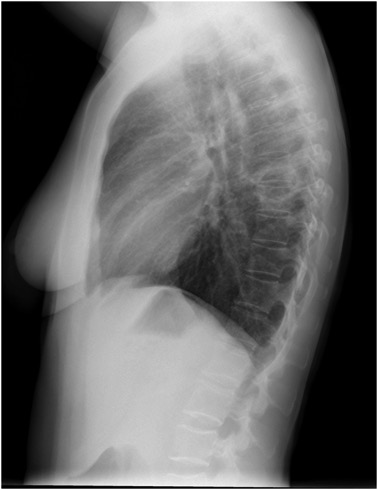

CASO: Febrícula y tos de 4 días de evolución.

Hallazgos:

- En la placa PA se observa una asimetría en los hilios pulmonares, el hilio izquierdo tiene una densidad aumentada.

- Tras examinar la placa lateral se observa un aumento de densidad en la columna que puede ser compatible con una condensación, es el signo de la desnificación vertebral.

SIGNO DE LA DENSIFICACIÓN VERTEBRAL: En la radiografía lateral normal, la densidad de la columna torácica tiende a disminuir desde la parte superior hasta el diafragma; la alteración de ese patrón por la presencia de una densidad superpuesta a la columna, indica la existencia de una consolidación pulmonar. Este signo adquiere especial valor cuando en la proyección posteroanterior la consolidación está oculta en el espacio retrocardíaco o en la base pulmonar.